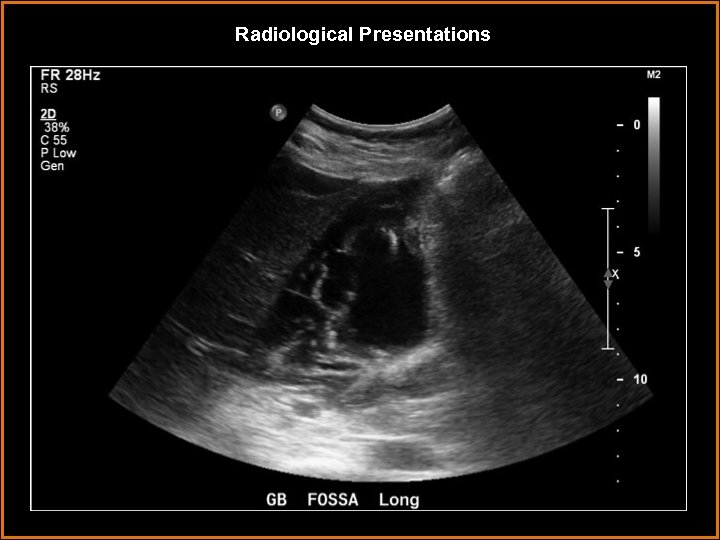

Findings and Differentials Findings: Striated thickening of the gallbladder wall with multiple hyperechoic, serpentine Findings and Differentials Findings: Striated thickening of the gallbladder wall with multiple hyperechoic, serpentine bands separated by hypoechoic areas. Also, intraluminal membranes concerning for desquamative mucosa. Differentials: • Acute cholecystitis – Wall thickening and pericholecystic fluid are neither sensitive nor specific. The most sensitive finding is a gallbladder stone with a positive Murphy’s sign. • Hydatid cyst – intrahepatic cystic lesion with floating membranes or multiseptated cysts. • Emphysematous cholecystitis – dirty shadowing from gas in gallbladder wall. • Volume overload – usually uniform, homogeneous wall thickening.

Discussion • Gangrenous cholecystitis is on the severe end of the spectrum of acute Discussion • Gangrenous cholecystitis is on the severe end of the spectrum of acute cholecystitis. • It is thought to be a result of tension in the gallbladder wall secondary to increased distention. This results in ischemic necrosis of the gallbladder wall, sometimes due to cystic artery thrombosis. • The condition occurs in older patients, usually male. Coexisting vascular disease is commonly seen. Sonographic Murphy’s sign is usually absent, thought to be due to devascularization and denervation. • On ultrasound, the primary finding is layered or striated gallbladder wall thickening. Usually, it is irregular with luminal projections. Less often seen, but more specific, are intraluminal membranes that are thought to represent desquamative mucosa.